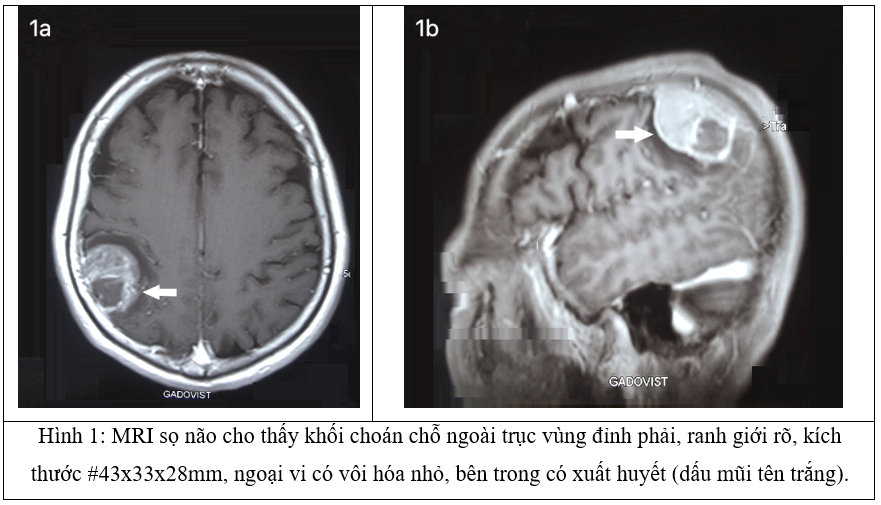

U màng não là khối u nội sọ, ngoài trục phổ biến nhất với tỷ lệ mắc 2,3-5,5/ 100.000 người, chiếm 20-30% của tất cả các loại u não nguyên phát ở người trưởng thành. U màng não liên quan đến xuất huyết trong u là rất hiếm gặp với tỷ lệ hiện mắc 0,5-2,4%. Bài báo cáo xin trình bày về một trường hợp lâm sàng: Bệnh nhân nữ 68 tuổi, vào viện vì đau đầu dữ dội kèm co giật. Chụp cắt lớp vi tính cho thấy tổn thương tăng tỷ trọng không đồng nhất #4x3x2,5 cm ở vùng đỉnh phải. Hình ảnh cộng hưởng từ não cho thấy khối tăng tín hiệu ngoài trục vùng đỉnh phải khoảng #43x33x28mm. Khối tín hiệu không đồng nhất, ngoại vi có vôi hóa nhỏ, bên trong có xuất huyết. Mô bệnh học cho thấy u màng não típ giàu tế bào kèm chảy máu (WHO I). Mục đích: Báo cáo về một trường hợp lâm sàng hiếm gặp: “Xuất huyết trong u màng não với triệu chứng co giật: chẩn đoán và hướng điều trị” để bổ sung thêm vào y văn hiện tại.

Chụp cộng hưởng từ não cho thấy khối choán chỗ ngoài trục vùng đỉnh phải, ranh giới rõ, kích thước #43x33x28mm. Khối tín hiệu không đồng nhất, ngoại vi có vôi hóa nhỏ, bên trong có xuất huyết. Sau tiêm ngấm thuốc mạnh không đồng nhất. Phần xuất huyết không ngấm thuốc. Dày màng não kế cận. Phù nề nhu mô não quanh cực dưới tổn thương, đường giữa không di lệch, không thấy bất thường hệ thống não thất (Hình 2).